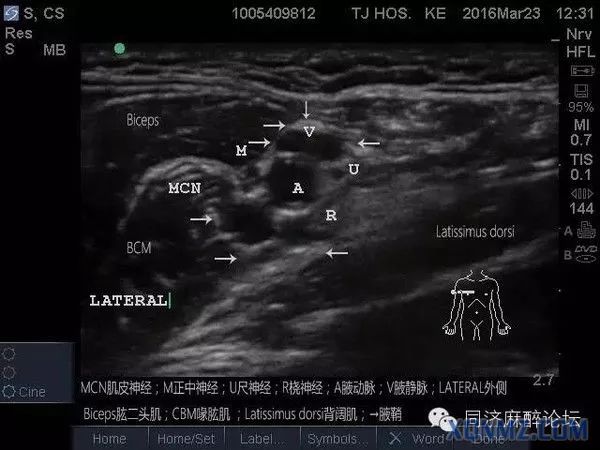

女患35岁,腕部肿物,做超声引导下腋路臂丛阻滞。

从解剖上看切口皮肤支配的神经是前臂内侧皮神经,而前臂内侧皮神经在腋窝的走行是腋动脉及腋静脉之间,所以超声下穿刺在进入腋动脉及腋静脉之间时,发现神经电刺激仪0.3就出现该区域皮肤震颤,给予局麻药5-10ml就可把手术做下来。